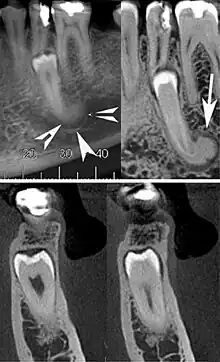

| Cone beam CT images showing a well-defined hyperdense round lesion attached to the root of supernumerary mandibular tooth (arrow head) with a surrounding hypodense rim.[1] | |

A cementoblastoma in a radiograph appears as a well-defined, markedly radiopaque mass, with a radiolucent peripheral line, which overlies and obliterates the tooth root. It is described as having a rounded or sunburst appearance. There is usually apparent external resorption of the root where the tumor and the root join. Severe hypercementosis and chronic focal sclerosing osteomyelitis are lesions to consider in the differential diagnosis of this lesion.